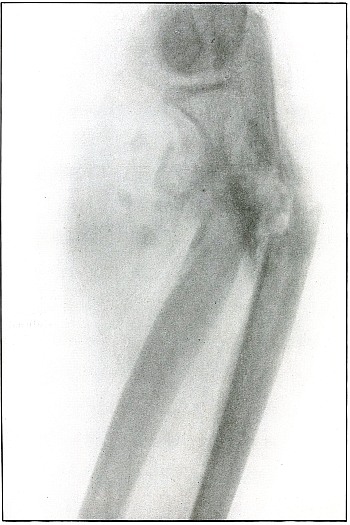

Plate 17.

[Pg 45]

Rifle—Plate 17.

UPPER EXTREMITY.

Gunshot Fracture of the Elbow.

The bullet in transverse course and high velocity through both bones

of the forearm struck the head of the radius, thus starting several

splitting lines of fracture and separating large fragments. Smaller

fragments which received some of the energy of the missile have been

carried along with it in turn, striking the ulna and carrying away

smaller fragments from it and causing the laceration which marks the

wound of exit.

Such wounds, with laceration of soft parts and fragmentation of the

bone, are prone to infection, against which treatment is directed. The

indications to be met are much like those of the wound shown in plates

18 and 19. Excision or

immediate methods of bone repair are contraindicated by infection.

Results will depend upon the nature and extent of infection.

[Pg 46]